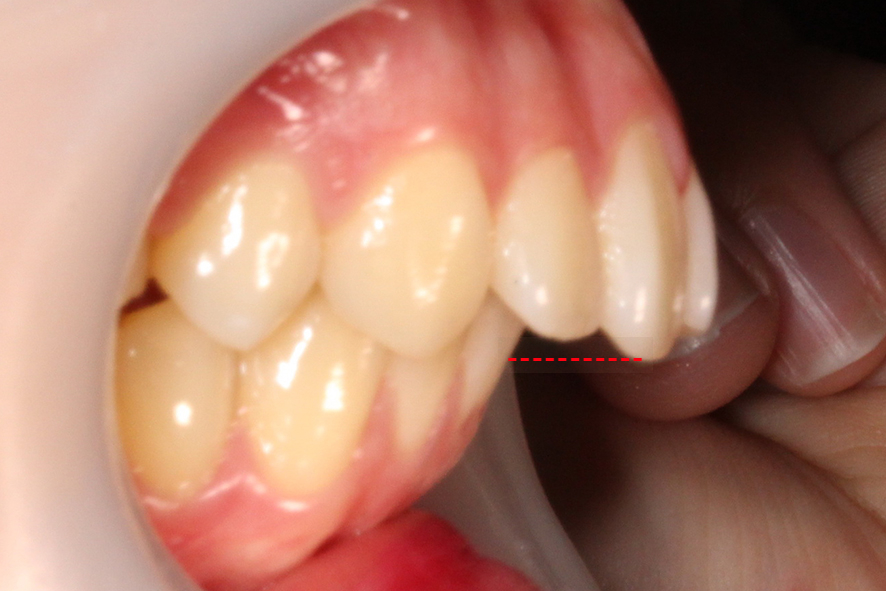

치아의 교합평면을 보면 구치부의

교합 상태가 정상적인 치아교합과

다른 모습을 확인할 수 있는데요,

상악이 하악보다 앞쪽으로 나와 있어

어금니의 상하악 교합이 어긋난 모습입니다.